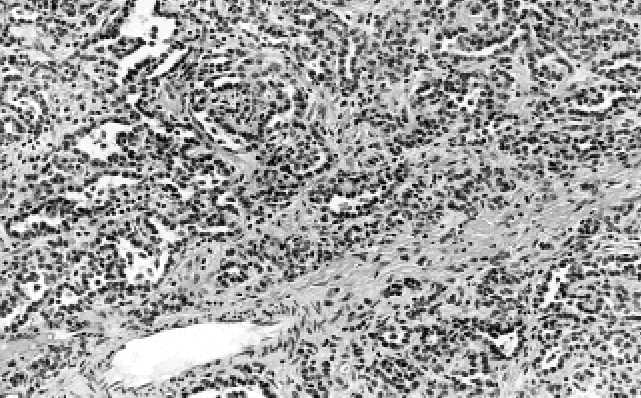

20 % případů. Asi polovina metanefrických adenomů obsahuje mikropapilární struk-

tury, které vyrůstají z drobných mikrocyst a napodobují tak nezralé abortivní glome-

ruly (Obr. C.3.3.). Všechny výše popsané organoidní struktury sestávají z jednoho

Obr. C.3.3. Asi 1/2 metanefrických adenomů obsahuje mikropapilární struktury.